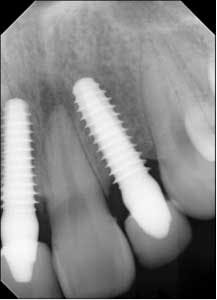

Fig. 6: Postoperative six weeks later.The patient returned for a follow-up eight months later (Fig. 7) and claimed she was careful not to bite into anything with her front teeth and wanted to know if they could be restored with permanent crowns. Impressions were taken and sent to the lab for fabrication of implant crowns. One year post-insertion, the final crowns and radiographs were taken (Figs. 8 and 8a).

Fig. 8a: One year post-insertion — final radiographs.